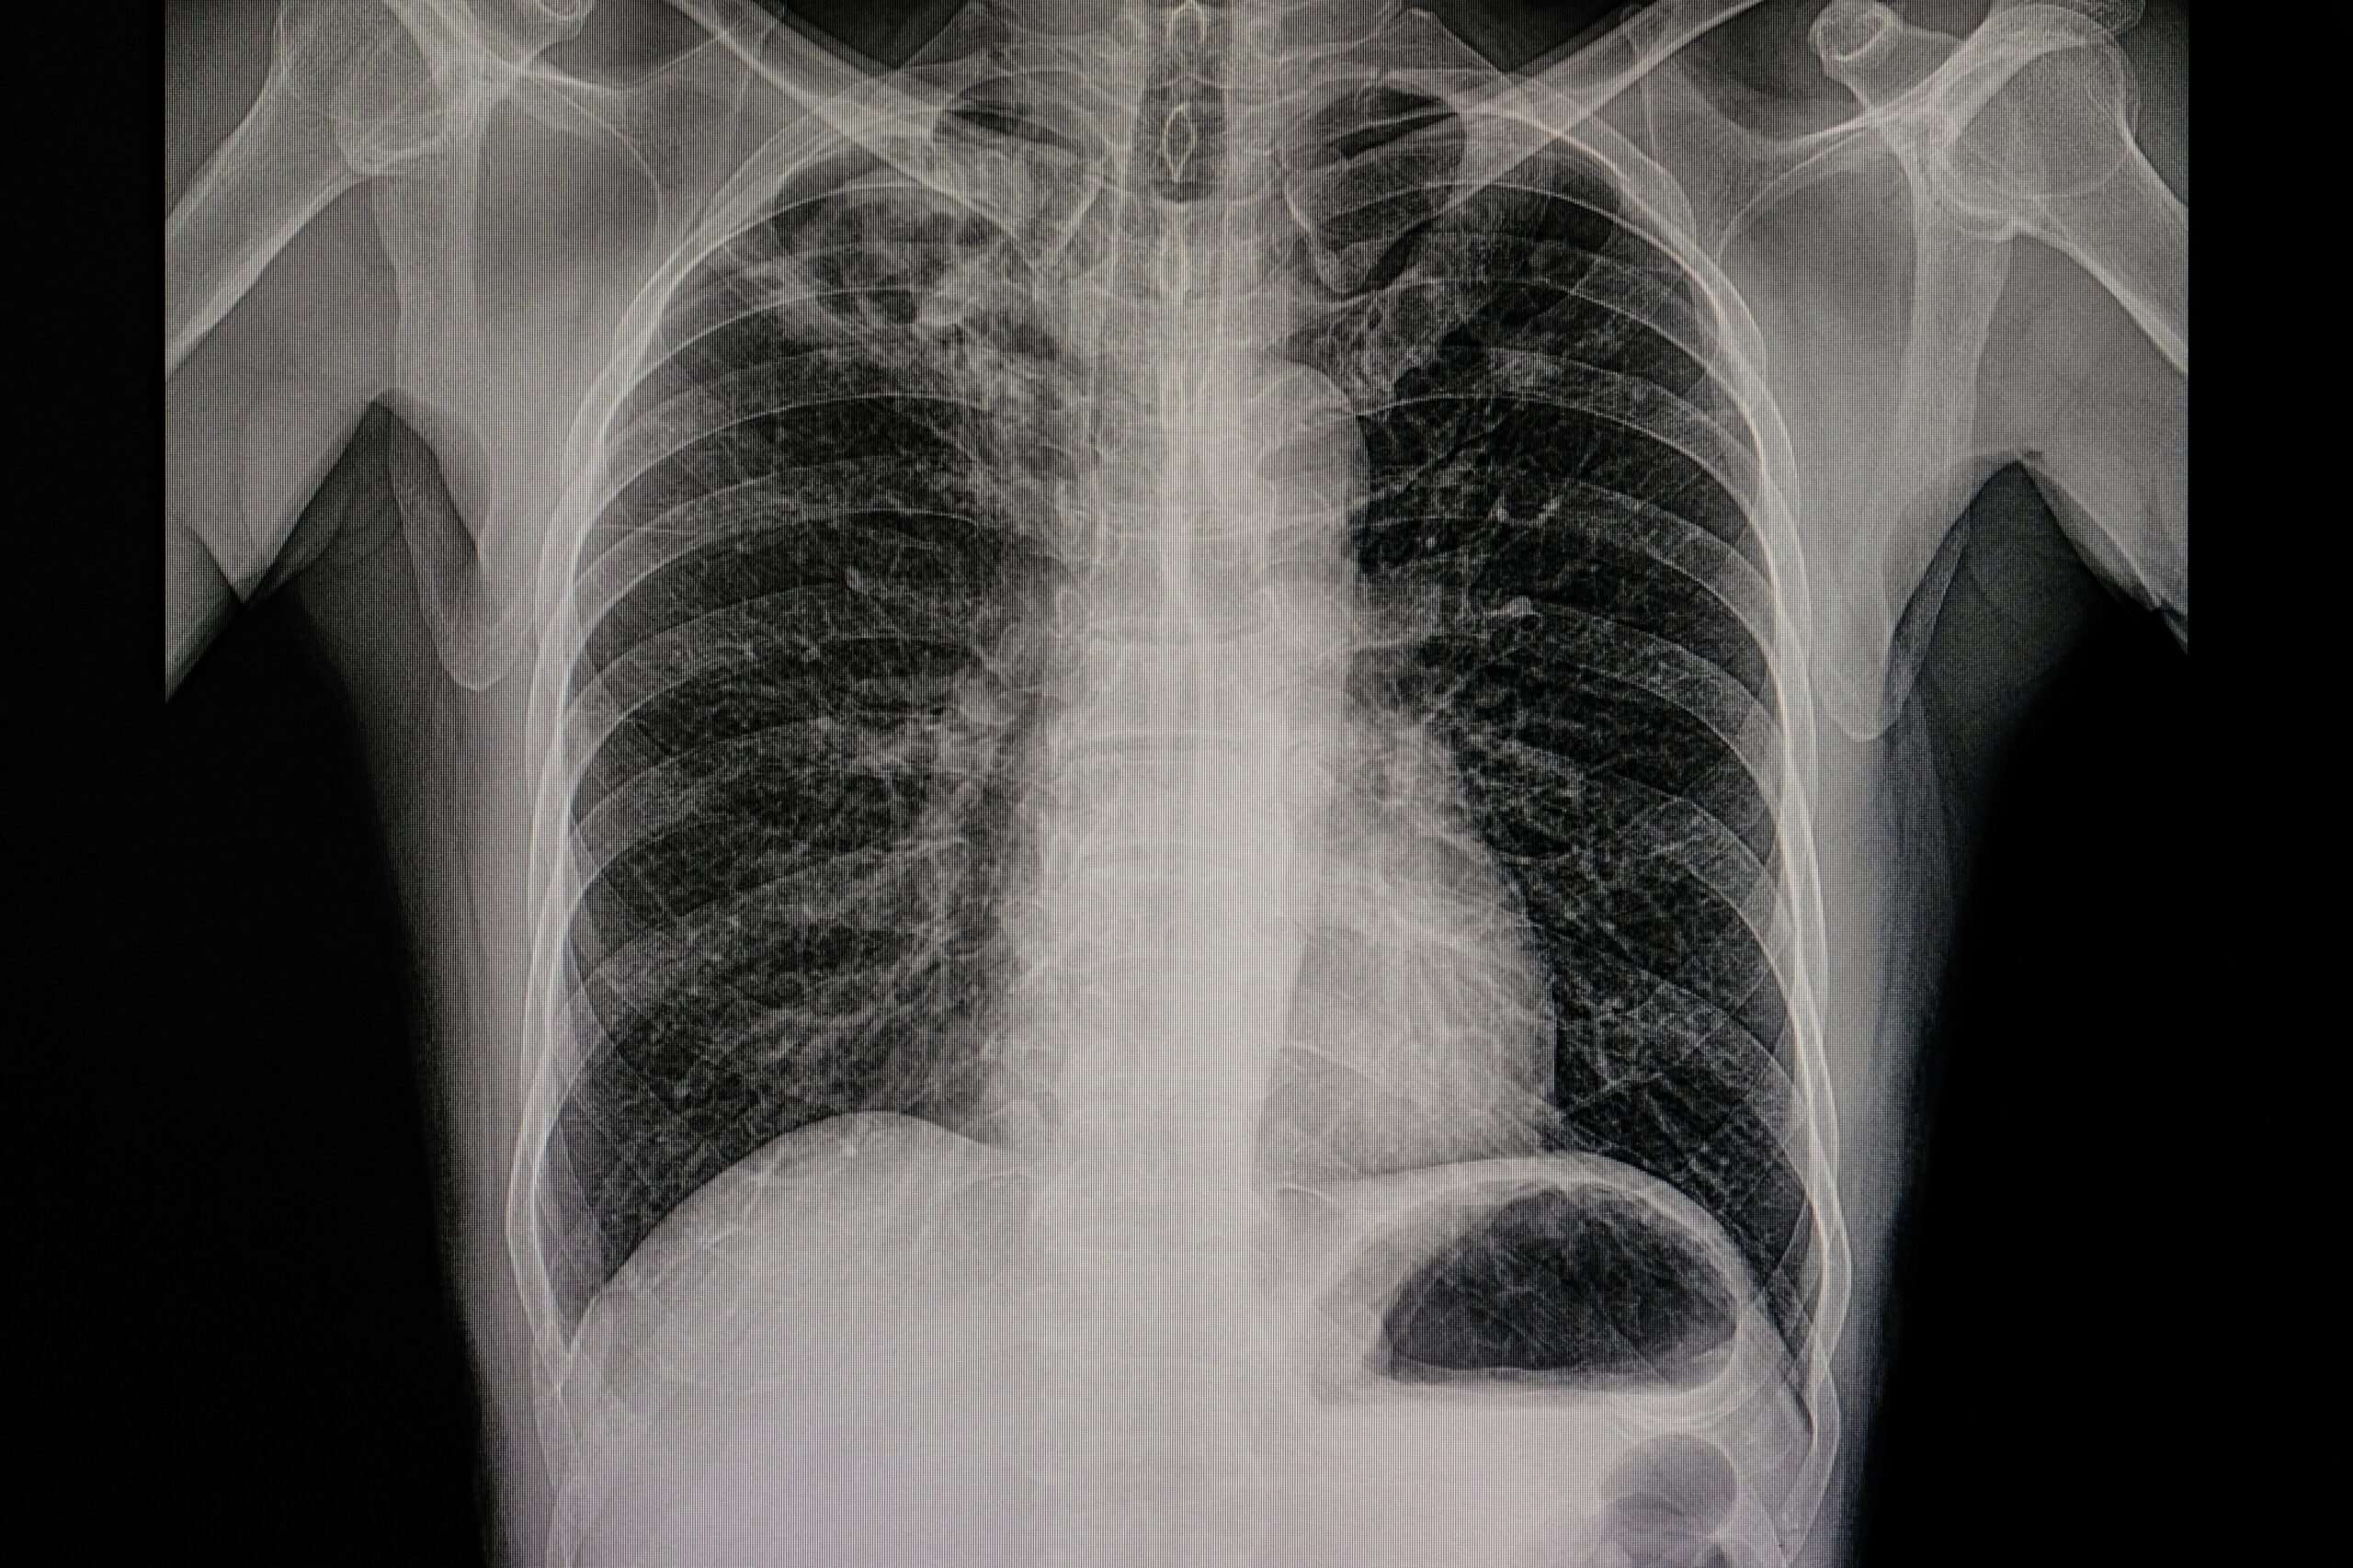

These small growths are quite common and can be seen on one in 500 chest X-rays and one in 100 CT scans of the chest. More so, CT scans of people over 50 who smoke will typically show chest nodules that look like a coin lesion or shadow in the lungs.

If your doctor identifies what appears to be abnormal growths in your lungs after an X-ray or CT scan, they will first need to determine whether the growths are benign or cancerous.

The doctor might request a chest X-ray or a CT scan based on a patient’s symptoms. Chest X-rays will allow your doctor to have a good view of the interior chest cavity, and if there is a questionable spot or shadow on a chest X-ray, the doctor may request a CT scan.

A CT scan will be very beneficial in this case as it can be used to capture images from different angles and depths and show deeper details of the body. This way, it will be easy to assess the nodule and diagnose based on its size and appearance.